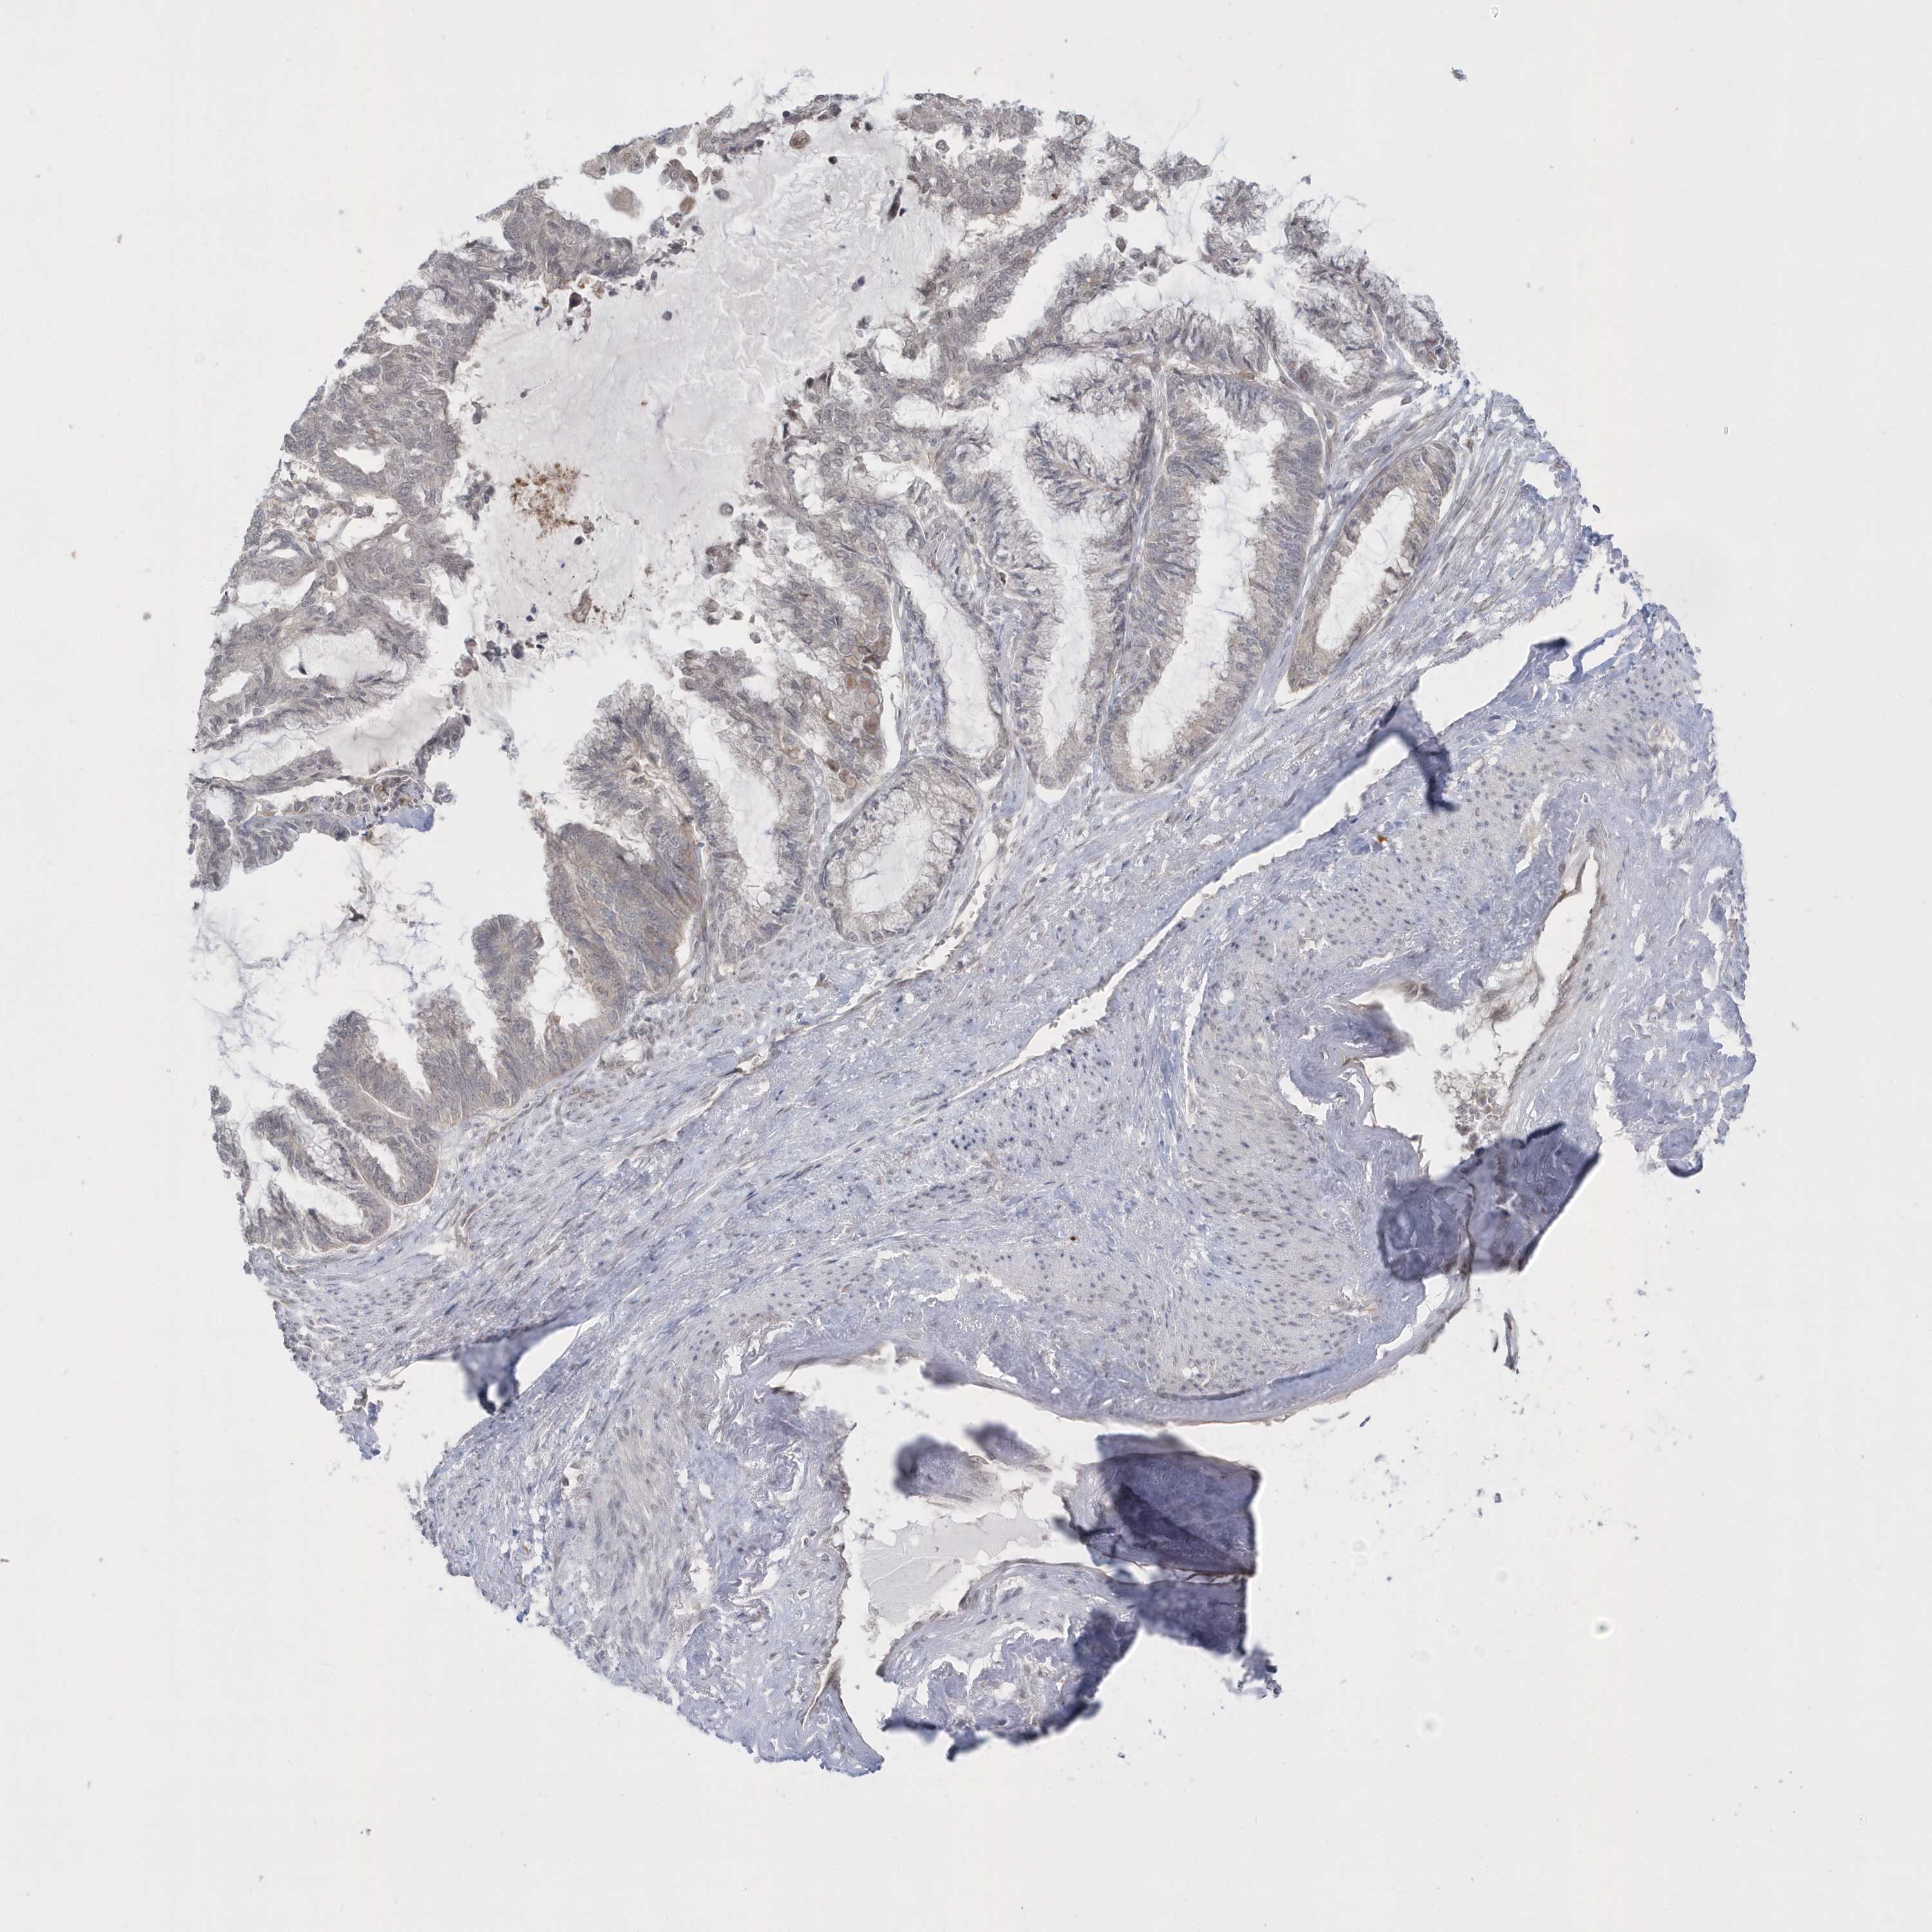

ENDOMETRIAL CANCER - Protein expressioni

A mouse-over function shows sample information and annotation data. Click on an image to view it in a full screen mode. Samples can be filtered based on level of antibody staining by selecting one or several of the following categories: high, medium, low and not detected. The assay and annotation is described here.

Note that samples used for immunohistochemistry by the Human Protein Atlas do not correspond to samples in the TCGA dataset.

Antibody stainingi

Antibody staining in the annotated cell types in the current human tissue is reported as not detected, low, medium, or high, based on conventional immunohistochemistry profiling in selected tissues. This score is based on the combination of the staining intensity and fraction of stained cells.

Each image is clickable and will lead to virtual microscopy that enables deeper exploration of all samples and also displays staining intensity scores, fraction scores and subcellular localization as well as patient and tissue information for each sample.

Antibody HPA036160

Staining

High

Medium

Low

Not detected

Intensity

Strong

Moderate

Weak

Negative

Quantity

>75%

75%-25%

<25%

None

Location

Nuclear

Cytoplasmic/membranous

Cytoplasmic/membranous,nuclear

Adenocarcinoma, NOS